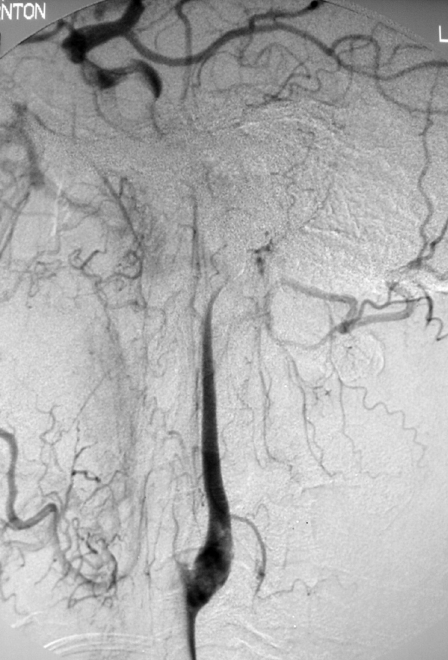

Figure 3.

Post stenting angiography of the left CCA showing restored flow into to the left ICA with restoration of normal intracranial flow. Note the persistent fetal type left posterior communicating artery.